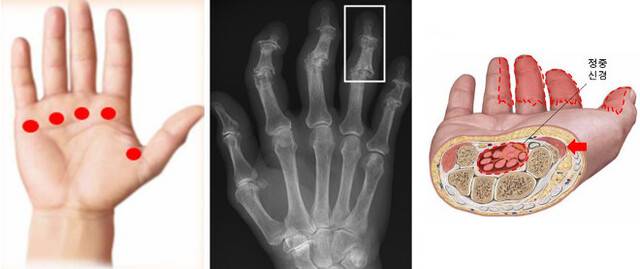

손가락이 저리거나 물건을 자주 놓치고 힘이 빠지는 느낌이 든다면 손목터널증후군을 의심할 수 있다. 손목터널(수근관) 내부의 손가락을 구부려주는 힘줄들이 붓고 두꺼워져 함께 있는 정중신경을 눌러서 발생한다. 엄지 검지 중지 약지의 끝이 찌릿찌릿 저리고 감각이 둔해진다. 손이 얼얼하고 터질듯한 느낌이 심해져 밤에 잠을 깰 정도면 이 병이 악화해 가는 신호다.

지난해 손목터널증후군으로 병원을 찾은 환자는 16만1360명으로 수부 질환 중 방아쇠수지 다음으로 많았다. 환자 수가 가장 많은 50대의 경우 여성이 남성보다 4배를 넘었다. 여성에게 흔한 이유는 남성보다 상대적으로 작은 손목터널의 공간을 갖고 있어 힘줄이 약간만 붓거나 두꺼워지더라도 쉽게 신경 압박이 가해질 수 있어서다.

여성의 폐경 이후 급격한 호르몬 변화 때문에 힘줄에 염증이 흔히 발생하는 것도 관련 있다. 치료는 신경 손상이 진행되기 전에 시작해야 한다. 방아쇠수지와 마찬가지로 질병 초기에는 약물치료가 가능하지만 점점 진행돼 마비 증상이 뚜렷해진다면 수술 치료를 고려해야 한다.